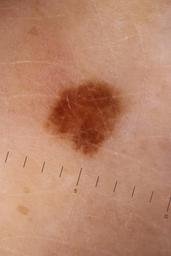

ISIC_5852089

Public

Information

- Created

- Dimensions

- 5184 x 3456

- Attribute to

- Sydney Melanoma Diagnostic Center at Royal Prince Alfred Hospital, Pascale Guitera

- License

- CC-BY-NC

- Used in

- Challenge 2020: Training

- Belongs to

- IP_9124285 IL_2074851

Clinical

| Field | Value |

|---|---|

| acquisition_day | 1173 |

| age_approx | 55 |

| anatom_site_1 | Lower extremity |

| anatom_site_2 | Foot |

| anatom_site_special | acral NOS |

| concomitant_biopsy | False |

| diagnosis_1 | Benign |

| diagnosis_confirm_type | serial imaging showing no change |

| fitzpatrick_skin_type | II |

| image_type | dermoscopic |

| lesion_id | IL_2074851 |

| patient_id | IP_9124285 |

| sex | male |